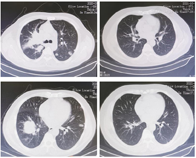

胸部CT显示:两肺多发弥漫性结节灶或多发球形病灶,边缘欠规整,密度均匀,以中下肺野及胸膜下区较多。为明确诊断,行腹部肿物切除术,术后病理报告:结合病史及免疫组化结果,考虑为转移性透明细胞癌,免疫组化示:肿瘤细胞:CK(+)、VIM(+)、CD10(部分+)、Ki-67(约20%+)、CD117(-)、Syn(-)。

至2021年10月12日最后一次返院复查,男性肿瘤指标未见异常。胸部CT示病灶几乎完全吸收。

故考虑三线治疗。患者拒绝参加临床试验,故予以卡瑞利珠单抗联合安罗替尼治疗,因服用安罗替尼出现明显胃肠道反应,患者拒绝继续服用此药。至2020年4月10日入院复查时患者咳嗽明显好转,胸闷症状好转,可自行下床行走,复查胸部CT病灶较前明显缩小,疗效评估:部分缓解(partial remission,PR)。故继续予以卡瑞利珠单抗免疫治疗维持至今。随访至2021年10月,复查胸部CT示病灶几乎完全吸收。出现几乎完全缓解(complete remission,CR)的疗效。可能是因为免疫检查点抑制剂激活免疫系统,增强抗肿瘤活性;同时免疫检查点抑制剂还具有药物不良反应少、患者生活质量高、抗肿瘤活性持久等优点。[4]。目前肾癌晚期的治疗,多以靶向或靶向联合免疫治疗为主,罕见单独免疫治疗取得良好疗效,是个体差异还是治疗的新方向?